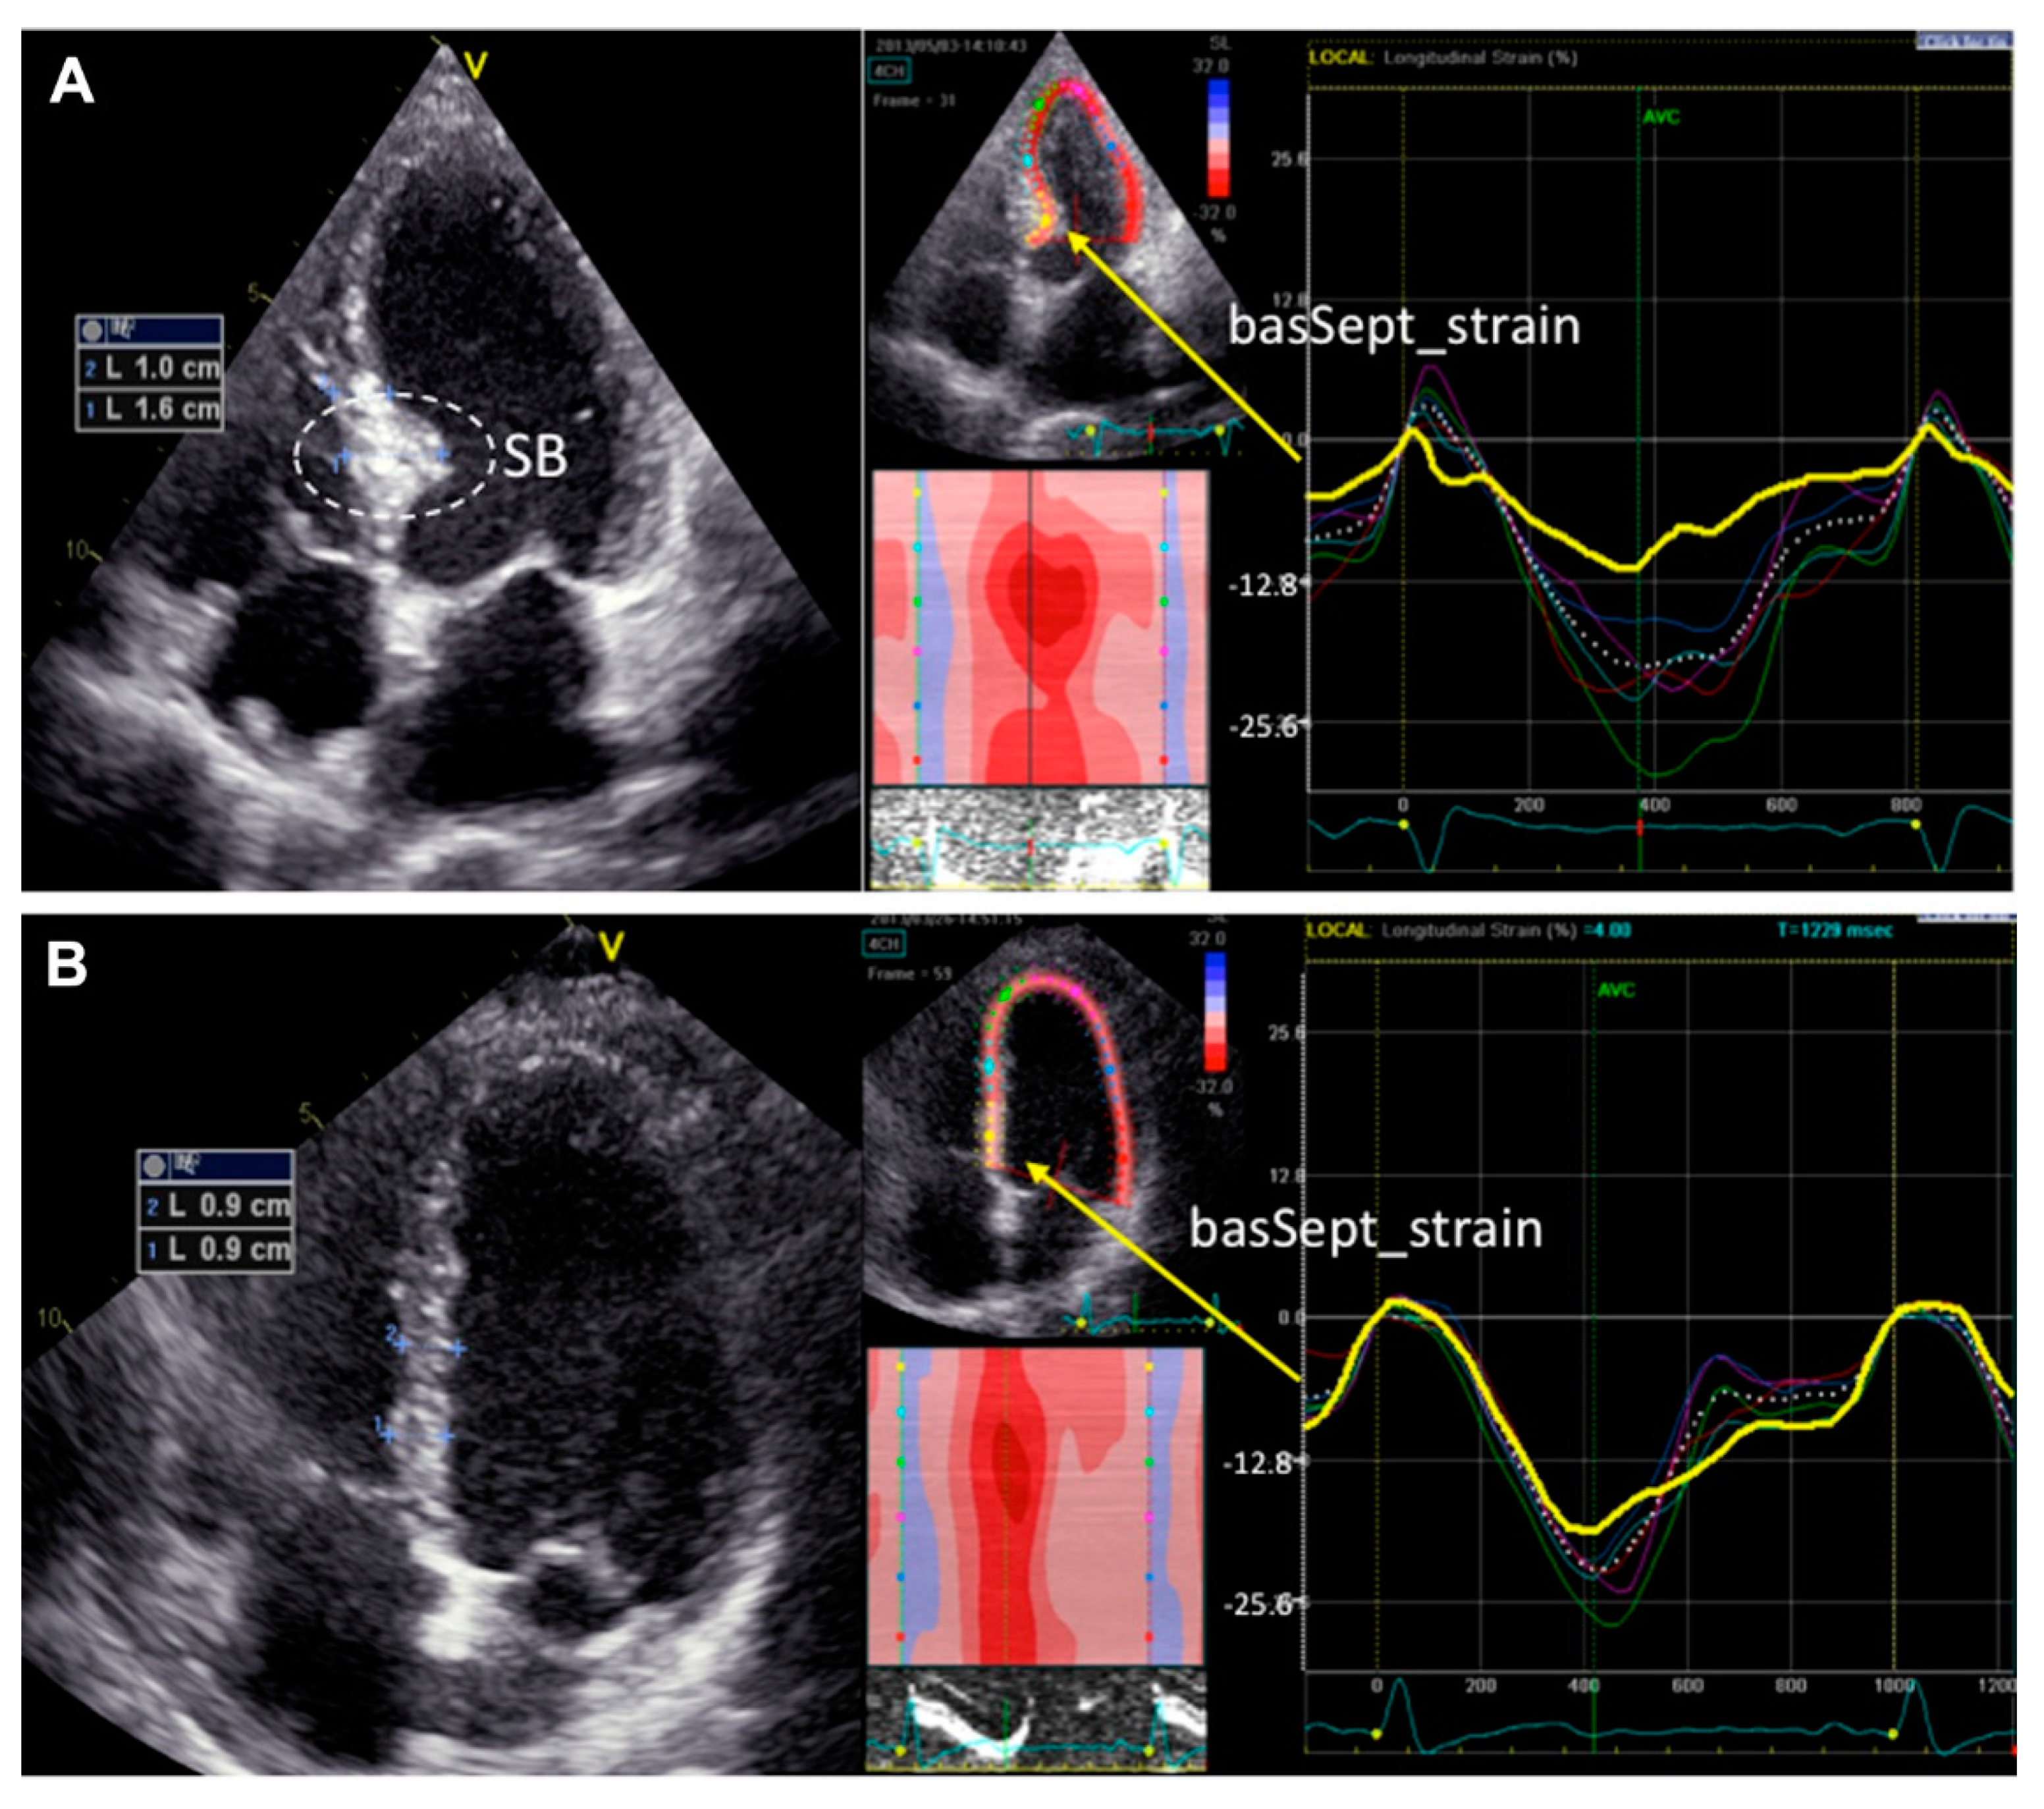

Basal septal hypertrophy (BSH) may be present in approximately 20–25% of patients with hypertension [47] or aortic stenosis [48], and is associated with a decrease in the regional myocardial deformation of the basal-IVS (Figure 2) [49]. In some patients, BSH may increase the risk of dynamic LVOT obstruction even in the absence of underlying hypertrophic obstructive cardiomyopathy [50]. Based on the above, BSH has been proposed as an early imaging biomarker of risk for the progression of hypertensive disease to heart failure [51]. However, the precise definition of the underlying BSH etiology is not always easy, especially in the elderly, where there is overlap between genetic and acquired causes of IVS hypertrophy [52].

Figure 2.

Examples of segmental longitudinal systolic strain curves derived from speckle tracing imaging in patients with (A) or without (B) septal bulge (SB). Gaudron PD, et al. J Am Soc Hypertens 2016; 10: 70–80 [49].